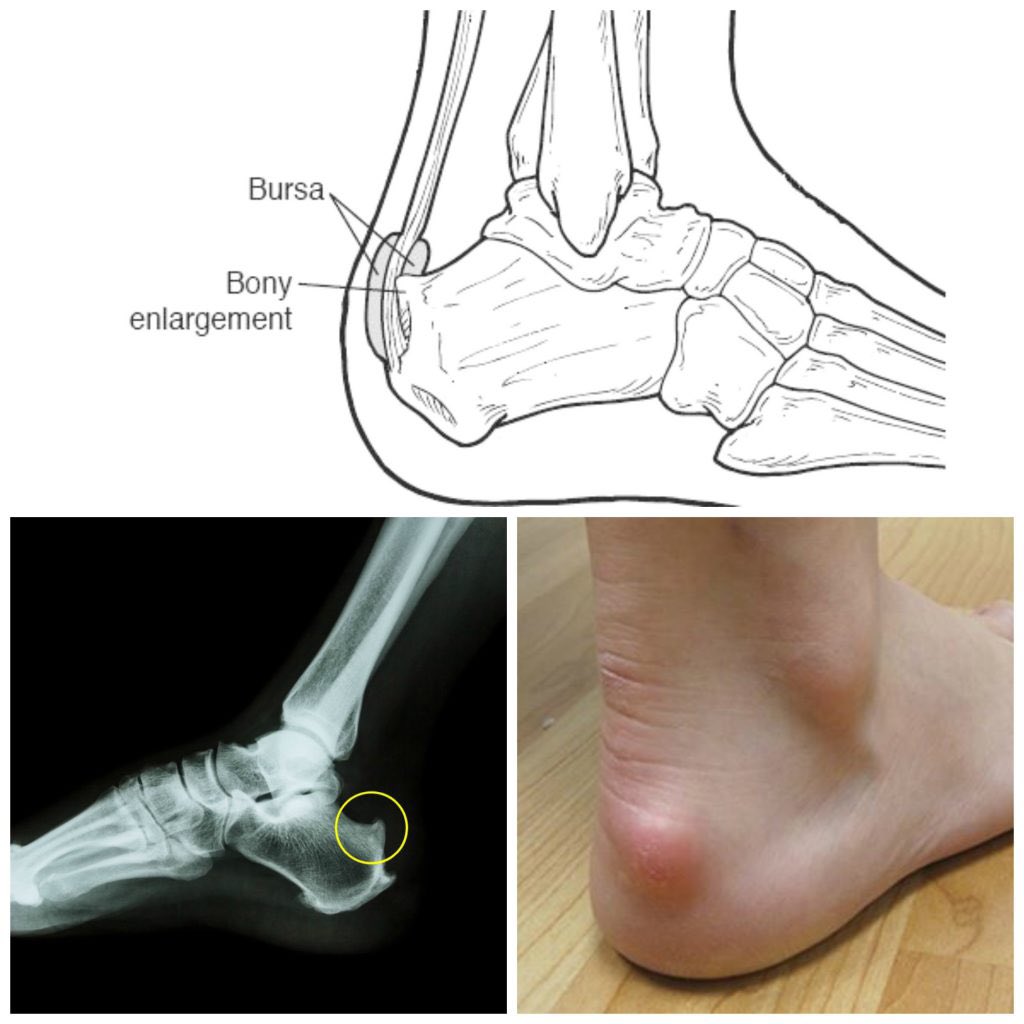

التشريح (anatomy)

نوعين من النتوءات العظمية ؛

* النوع (A)نتوءات داخله ع فوق plantar facia

*النوع (B) داخله مع plantar facia

* النوعA أطول بكثير إحصائيًا من طول النتوء للنوعB ، مع كذا المرضى الي يعانون من نوعB اكثر الم من A

نصنفها ٣ انواع

نختصرها ب صوره